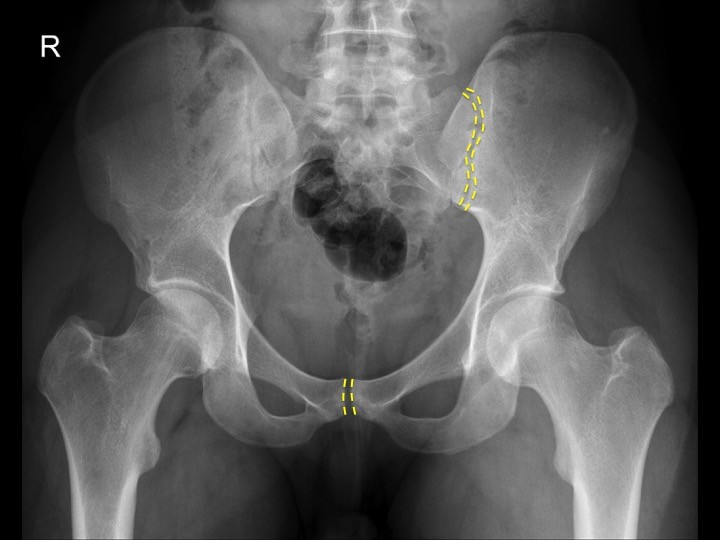

Patolojilerin bir çoğunu bulunduran bir örnek üzerinde özetle yukarıda anlatılanlara dayanarak klinisyen olarak nasıl bir yorum yapacağımızı aşağıdaki grafide sizlerle paylaşalım.

- Öncelikle hastanın ismi, çekim tarihi, saati gibi önemli tanımlayıcı hasta bilgileri olmadığı için bu grafi ideal bir grafi değil. Bunun dışında lomber 4-5. vertebraların grafi içinde yer almaması, femur 1/3-1/4 proksimal kısımlarının bilateral yer almmaması, her iki ilium un tam olarak kasete yerleşmemiş olması da bu grafinin iyi bir grafi olmadığının ve görünmeyen alanlarda var olan fraktürleri gözden kaçırabileceğimizin uyarısını veriyor. Nasılsa grafiye L işareti koyup sol taraf olduğunu belirtmişler… bunun için teşekkür ederiz. KLİNİSYEN OLARAK – BU GRAFİ TEKRARLANSA İYİ OLUR DİYE DÜŞÜNEBİLİRSİNİZ DOĞAL OLARAK. Ama çoğu zaman bu yetersiz grafilere bakmak durumunda kalıyoruz Türkiye’de bir çok Acil Serviste ne yazıkki. Travma hastalarının yatak başında gerçekleştirilen çoğu grafisinin kalite sorunları içerdiğini baştan kabul etmek de gerek sanırım.

- Şimdi şu 3 temel halkamıza bakalım. Hem ana pelvik halkanın hemde 2 obturator halkasının bozuk olduğuna ve devamlılık arzetmediğine dikkat ediniz. Soldaki obturator halkası sağdakine oranla nisbeten daha düzgün görünüyor. Bu halkalardaki devamsızlık fraktürü düşündürmeli demiştik, ama bu grafi de zaten herşey çok bariz bir şekilde gözler önünde. HALKALARDAKİ BU BOZULMA = KANAMA İÇİN UYARAN AYNI ZAMANDA.

- Eklemlerin kontrolüne bakacak olursak. Symphisis pubisteki ayrılmanın ne kadar korkutucu olduğunu idrak edebiliriz sanırım. Neredeyse 5 cm’ye varan bir ayrılma bu bölgedeki genitouriner yaralanma olasılığınında bir göstergesi. Sacroiliak eklemlere arka tarafta bakacak olursak solda yer alan ile sağda yer alan arasında genişlik olarak ciddi bir fark göze çarpıyor. Kaldı ki daha sonra değineceğimiz sacrum foramenleri sağ tarafta zaten ciddi bir hasar görmüş durumda. AÇIK KİTAP OLARAK DA ADLANDIRILAN BİR KIRIK BU HASTADAKİ. ANA VASKÜLER YAPILARIN POSTERIORDA SEYRETTİĞİNİ DÜŞÜNÜRSENİZ, KANAMANIN ŞİDDETİNİ AZ ÇOK TAHMİN EDEBİLİRSİNİZ.

- Acetabulum kontrolü. Hatırlayacağınız gibi burada 6 adet önemli alandan bahsetmiştik. Sağda ve solda iliopectineal yada iliopubic hatta ki bozulmayı farkettiniz sanırım, tabiki sağ tarafta pubic deplasman çok daha bariz bir biçimde görünüyor. Bu çizgilerdeki bozulma bize acetabulumda anterior kolon fraktürü düşündürmeli. Her iki tarafta da Ilioischial çizgide bariz bir düzensizlik farkedemedim açıkçası, yani posterior kolonda şu an itibariyle bir sorun yok diyebiliriz. Sağ ve özellikle sol tarafta acetabuler tavan çizgisinde, ön ve arka sınır çizgilerinde çok net bir düzensizlik görülmüyor. Solda ve sağda göz yaşı bulgusu farkediliyor. ONCA YARALANMA VARKEN ACETABULER ALANDA BİR KIRIK OLUP OLMADIĞININ DİĞERLERİ KADAR NET OLAMAMASI SİZİ HAYAL KIRIKLIĞINA UĞRATMASIN. VAR OLANLAR ZATEN ACETABULER BİR YARALANMANIN DA BU HASTADA YÜKSEK OLASILIKLA EŞLİK EDEBİLECEĞİNİN BİR GÖSTERGESİ. Kaldı ki sağda ve solda ön kolon yaralanmasını gösteren bulgular mevcut.

- Sacral foramenler sağda soldakilerle kıyaslandığında oldukça cidi bir biçimde hasara uğramış bir durumda izleniyor. Hatta sacrumun yukarıdan aşağı doğru net biçimde ayrıldığını ifade etmek yanlış olmaz. YİNE POSTERİOR SEGMENT YARALANMALARI = CİDDİ KANAMA. Her ne kadar pelvis yaralanmalarındaki kanamalar %85-90 Venöz kanamalar olsa da yaralanan damarların boyutları kanamanın şiddetini de belirliyor haliyle.

- Proksimal femura bakacak olursak, iki taraf içinde tam bir değerlendirme yapmak mümkün olamayacak ama sağda ve solda SHENTON çizgisinin düzgün izlenebildiği görülüyor. Trabekuler yapılar çok iyi değerlendirilemiyor grafinin kalitesi nedeniyle. Femur boynu ve başı etrafında korteks bilateral düzgün izlenebiliyor. Bilateral küçük trochanterler izlenebilirken, büyük trochanterler ile ilgili bişey söyleyebilmek bu grafide zor. BU HASTADA CİDDEN FEMURLARDA HASAR OLUP OLMADIĞINI ANLAMAK İÇİN EK GRAFİLERE İHTİYAÇ VAR.

- İlium’a baktığımızda her ne kadar sağda tam grafi içinde yer almadıysa da görünen alan içinde bir fraktür izlenmiyor fakat sola baktığımızda acetabulumun hemen üstünde uzanan lineer bir fraktür hattı mevcut. Yine tek tek kemiklere bakacak olursak her iki pubik raminin ve ischiumun, sacrumun net kırıklarını görebiliyoruz. Hatta sağda L5 iö muhtemel transvers procesinin fraktürü olabilecek bir kemik parçası sağ sakroiliak eklemin hemen üzerinde bir lokalizasyonda duruyor. Grafi kalitesi ve içerdiği alanlar yetersiz olduğundan pelvis etrafındaki yumuşak dokularla ilgili bir yorum yapmak mümkün değil.

Şimdi bu grafide son derece ciddi hasarlarla karşı karşıyayız. Tabiki her pelvis grafisi bu kadar bariz, abartılı birden fazla yaralanmayı birlikte bulundurmuyor. Bunlardan bir tanesi yada iki tanesi çok hafif, silik bulgularla da grafilerde yer alabiliyor. Bizlere düşen ister bariz ister silik klinik bulgular olsun, tüm grafileri sistematik bir biçimde değerlendirmek, şüpheli olan herhangi bir görüntü için varsa Radyoloji uzmanı arkadaşlarımızdan görüş almak ve/veya ileri inceleme tekniklerine yönelmek olacaktır ki çoğu olguda bu ileri teknik BT olarak tercih edilmektedir.